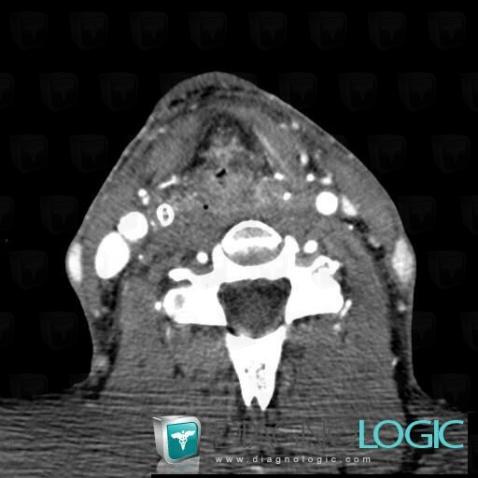

Postradiation edema, Oropharynx / Floor-mouth, CT

Here is the specific information in the key image above:

- Diagnosis Postradiation edema, Location(s) Oropharynx / Floor of mouth, with gamuts